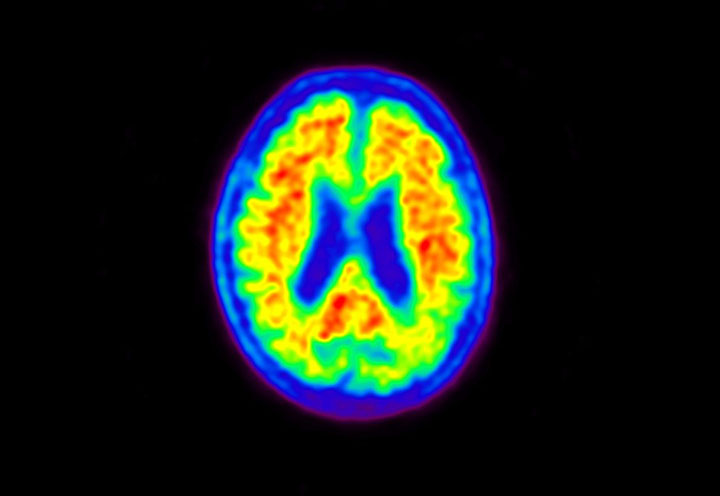

Head / Case5 : Amyloid

Courtesy : Kindai University Hospital

- Imaging protocol

- Injected dose: 4.27 MBq/kg, 18F-Flutemetamol

- Uptake time: 99 minutes

- Scan time: 20 minutes